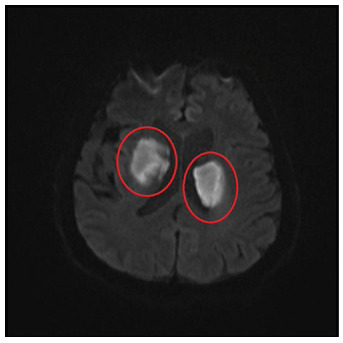

A 72-year-old male patient presented with a decreased level of consciousness. He had no known history of systemic disease. He also had a painful vesicular rash on the scalp three weeks prior that had resolved. His neurological examination, during which he could not respond to verbal stimuli, revealed that his four extremities responded to painful stimuli and that the plantar reflex was downgoing bilaterally. His body temperature was 37.3°C. Diffusion-weighted magnetic resonance imaging (MRI) revealed infarcted areas, indicating diffusion restriction in both suprathalamic regions (Figures 1 and 2). A lumbar puncture was performed. No cells were observed upon direct examination of the cerebrospinal fluid. The microprotein levels were high at 65.4 mg/dL. Polymerase chain reaction (PCR) for varicella zoster virus (VZV) DNA was positive. Serum VZV IgG >1500 mIU/mL was positive, and serum VZV IgM was 2.2 mIU/mL was negative. The patient was given 10 mg/kg acyclovir three times daily for 21 days and 60 mg/kg methylprednisolone for 14 days. The patient began to respond significantly to verbal stimuli in the fourth month of hospitalization. VZV can spread centrally from the peripheral nerves, causing neurovascular disorders ranging from ischemic stroke-related large-vessel vasculopathy to arterial dissection and subarachnoid hemorrhage1. VZV vasculopathy is often chronic and long-lasting. Clinical improvement is possible with antiviral therapy2. Given that VZV is a treatable cause of stroke, its etiology should be investigated even if the rash is not described.

FIGURE 1: Hyperintense areas in bilateral suprathalamic regions in B1000 sequence on diffusion-weighted MRI.

FIGURE 2: Hypointense areas consistent with diffusion-limiting ischemia in bilateral suprathalamic regions on diffusion-weighted MRI ADC sequence.